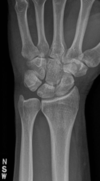

Fratura de Chaffeur

Fratura do processo estilóide do rádio.